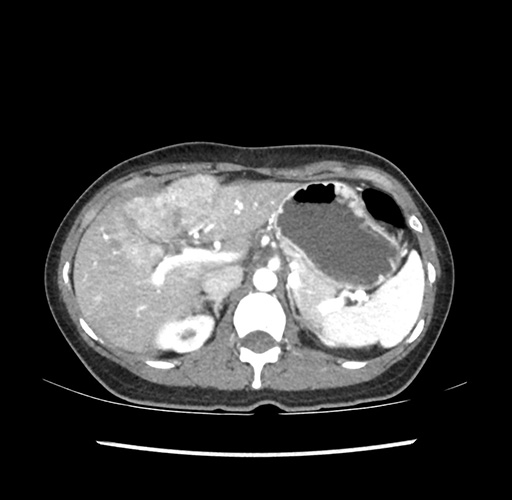

Imaging Analysis

Look through the patient's CT scan to identify any areas of concern for the necessary procedure.

Based on your CT findings, which issue(s) would give reason for "planned slowing down moment(s)" in this case?